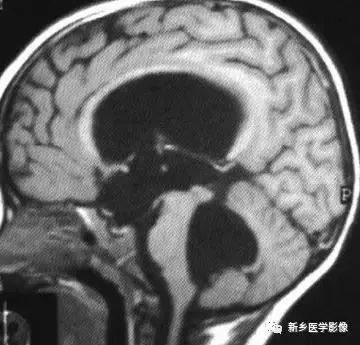

❷ 小脑扁桃体下疝畸形

又称Chiari's畸形,即小脑扁桃体下移到椎管内,延髓、四脑室延长并部分向下移位。可分为3型。各型均常有脑积水表现。

Ⅰ型:若仅有小脑扁桃体下移。扁桃体下缘低于枕大孔连线5mm以上,无脑干及四脑室改变者为Ⅰ型。

Ⅱ型:除小脑扁桃体下移外,同时有四脑室部分或全部降入枕大孔以下者为pⅡ型。

Ⅲ型:全小脑及四脑疝入枕大孔以下者为Ⅲ型。

❶ 交通性脑积水

又称脑室外梗阻性脑积水,是由四脑室出口以后脑脊液循环通路障碍所致的脑积水。常位于蛛网膜下腔,以基底池最常见。

主要原因包括脑膜炎、蛛网膜下腔出血、脑膜转移、外伤、静脉窦血栓、颅脑手术后和脑脊液吸收功能障碍等。临床表现主要由颅压增高所引起.,可表现有头痛、呕吐、复视和视乳头水肿等。

交通性脑积水时,第四脑室扩大通常出现较晚,故早期时,可仅表现有侧脑室和三脑室扩大。主要应与导水管狭窄之梗阻性脑积水区别。MR矢状位T1加权图是直接观察导水管有无狭窄的最好方法。

另外需要与普遍性脑萎缩区别:脑萎缩时沟脑裂增宽,而脑积水时脑沟变窄消失或正常;脑萎缩时三脑室扩大较明显,脑积水时三脑室扩大不明显。到晚期,交通性脑积水出现整个脑室系统普遍扩大,而脑沟正常或变窄消失。